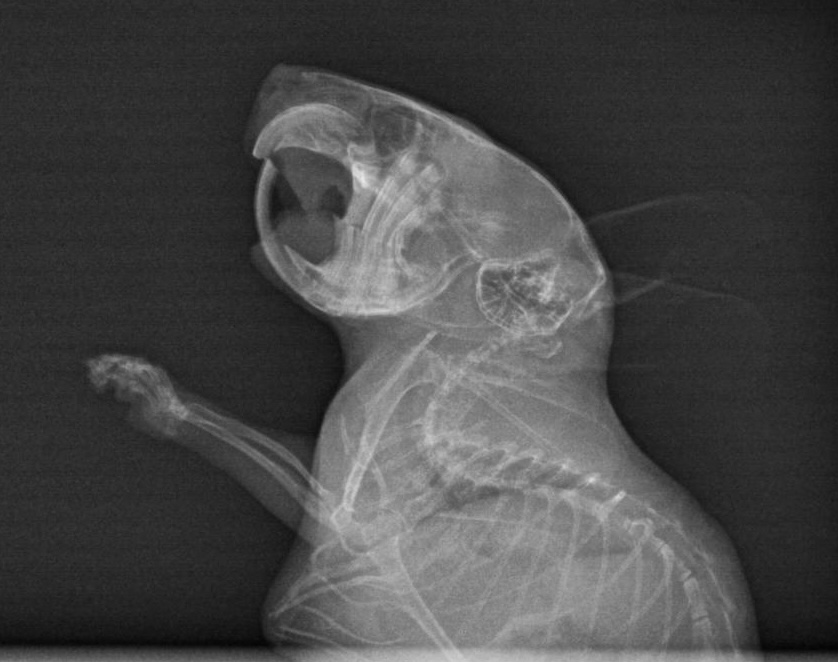

Also bin ich mit ihr am 15. Oktober zum Tierarzt gefahren und habe sie dort zusammen mit Freundin Leni abgegeben. Mit der Bitte die Zähne wirklich gut zu checken und auch ein Röntgenbild anzufertigen.

Mittags dann der Anruf: Klein Ida hat sich den Kiefer gebrochen. Mist, mist, mist! Tja nun... was ist hier die beste Lösung. Die Tierärztin und ich schweigen erst einmal... wägen ab. Doch wir sind uns einig, dass die kleine Maus eine Chance bekommen soll. Somit werden nur die vorderen Schneidezähne etwas gekürzt, da diese schon etwas zu lang waren und ansonsten bleibt uns nur die Versorgung mit Schmerzmittel und Brei.

Hier die Bilder, ich habe extra gefragt, ich darf sie teilen. Ich sehe darauf nix, aber ihr vielleicht